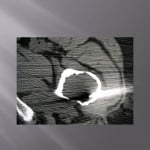

Biopsie sous guidage scanner